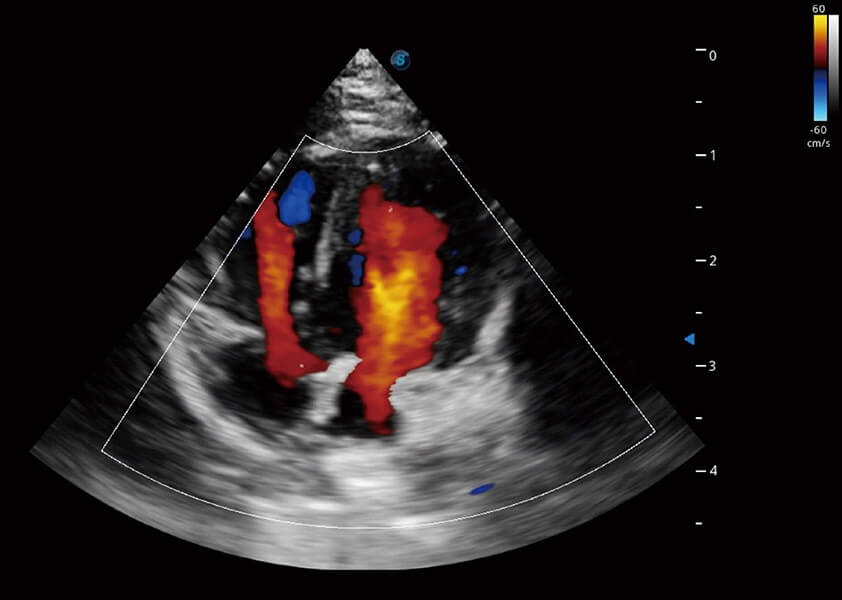

ProPet 60 作为一款高端台式动物超声设备,为动物医生的日常诊断提供了一系列贴合动物临床需求、解决临床实际问题的高级成像功能。凭借全系列高清探头,满足医生对腹部、心脏、生殖、浅表、肌骨等成像的所有需求,切实帮助您提升检查效率,提高诊断信心。

动物是人类最亲密的朋友和最值得信赖的伙伴。milan米兰也一直致力于探索动物专用的超声影像解决方案。 全新推出的ProPet系列,是milan米兰在动物超声影像智能化、专业化、精准化的一次跨越式革新。动物不能用言语来表述自己的不适,通过超声影像,ProPet系列搭建了动物医生与不同物种沟通的“桥梁”,为动物医生注入了“治愈之力”。